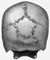

Череп с т. н. костью инков.

Инков кость, одна из аномалий черепа человека — отделённая швом верхняя часть чешуи затылочной кости. Имеет вид многоугольной вставки. Название возникло вследствие того, что эта аномалия была впервые обнаружена на черепах древних инков Перу. Однако она распространена у представителей всех человеческих рас (до 10% случаев). Встречается дополнительное деление И. к. на 2—4 части по числу центров окостенения.